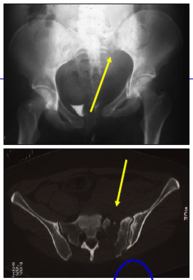

Was für Untersuchung und Diagnostik macht man? Anamnese & klinische Untersuchung. Röntgen: Beckenübersicht a. p. und CT: insb. bei Verdacht auf Verletzungen im Bereich des hinteren Beckenrings oder komplexen Beckenverletzungen

Wie sehen Frakturen Typ A - C aus?

Was macht bei einem akuten Beckentrauma? Nenne vier Schritte: 1) Klinische Untersuchung, aber keine klinische Untersuchung der Becken-stabilität! 2) FAST: Sono Abdomen 3) Polytrauma/Mehrfachverletzung: Spiral CT mit KM 4) Isolierte Beckenringverletzung: Beckenröntgenserie